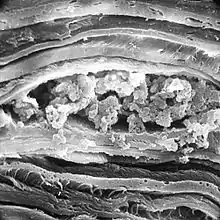

По окончании развития глаза в строме образуется согласованная сеть кератоцитов, объединенных дендритными отростками.[3] Кератоциты в состоянии покоя синтезируют так называемые кристаллины — молекулы, изначально более известные благодаря своей роли в хрусталике глаза. Как и в хрусталике, кристаллины стромы предположительно позволяют поддерживать оптимальную прозрачность и рефракцию света в роговице,[4] а также составлять часть антиоксидантной защиты роговицы.[5] Описана экспрессия кератоцитами человека таких кристаллинов, как ALDH1A1, ALDH3A1,[6] ALDH2 и TKT (транскетолаза). Для разных видов характерны разные наборы производимых в строме кристаллинов.[7] Выделяемый в толщу стромы кератансульфат может играть несколько ролей, в том числе роль динамического буфера, поддерживающего оптимальную гидрацию;[8] при генетическом нарушении его синтеза развивается пятнистая дистрофия роговицы.[9]